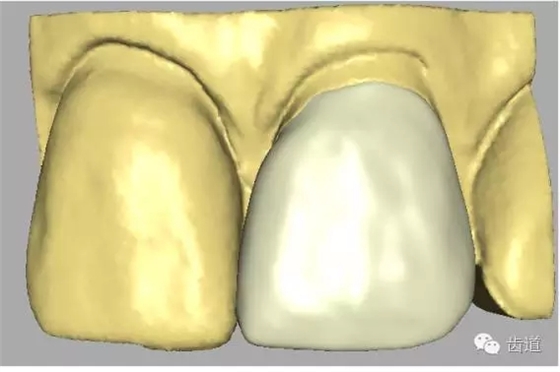

二)確認(rèn)在代型上完全就位:

全冠僅邊緣與代型接觸,其余內(nèi)表面與代型表面間隙大小為30-40μm。

四)人造冠就位 1、理論標(biāo)志

人造冠內(nèi)表面與患牙面間隙不大于50μm。 2、參考標(biāo)志